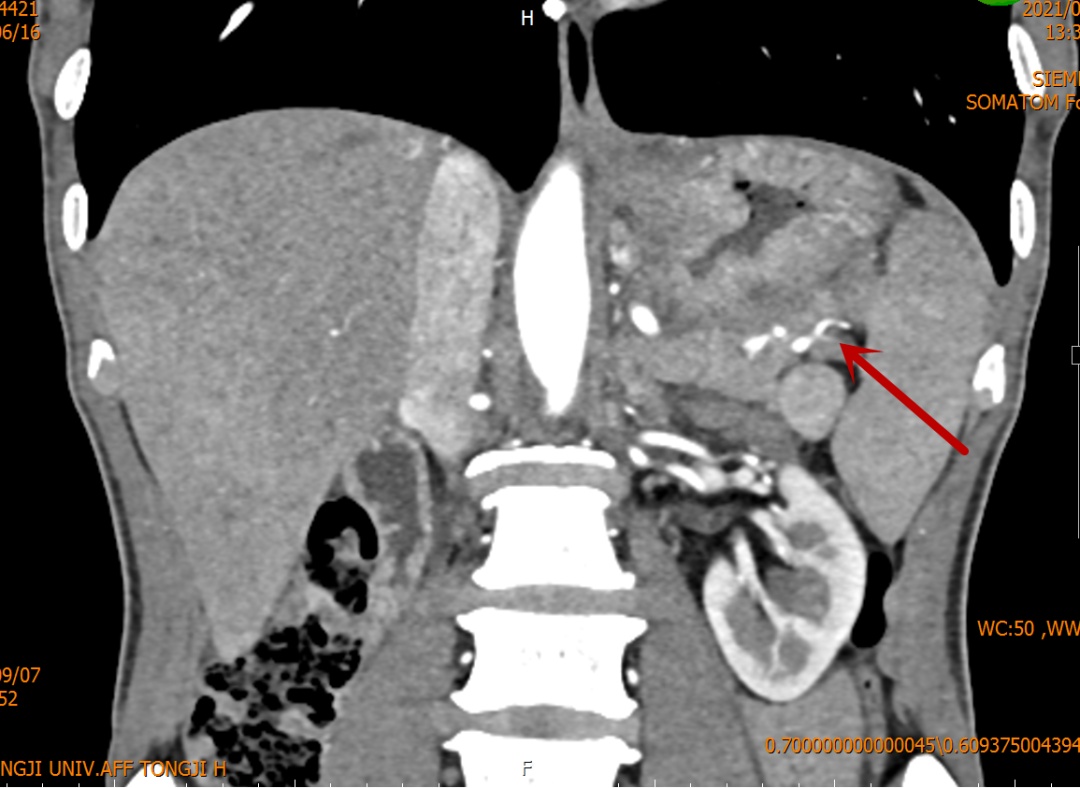

患者为一位60多岁男性,因“纳差,消瘦三月余”在当地医院行胃镜检查提示:胃底、贲门肿瘤;CT检查发现肿瘤体积较大,侵犯胰腺及脾门可能。患者家属慕名来到同济医院找到施宝民主任就诊。

施主任接诊病人后,尽快安排患者住院并完善术前检查。增强CT等影像显示胃部肿瘤体积较大,浸润范围广,位于胃底、胃体直到贲门,向后已经侵犯脾动静脉脉及脾门,与胰腺体尾部浸润成一团。单纯全胃切除术不能完整切除肿瘤,而必须联合三脏器切除(全胃+脾脏+胰腺体尾部)做整块切除。但手术难度大,创伤大,给医患双方都是巨大挑战。开腹手术切口长、创伤大,腹腔镜腔镜手术的切口小、创伤相对较小,但对手术团队腹腔镜外科技术要求更高。最终结合患者一般情况,经全科医生讨论后,决定实施腹腔镜辅助下全胃切除术+脾脏切除术+胰体尾部切除术+淋巴结清扫术。在麻醉科韩松副主任医师的精准麻醉和通力配合下,施宝民主任带领团队成员林锐、季堃主治医师用时4个多小时,顺利完成了手术。